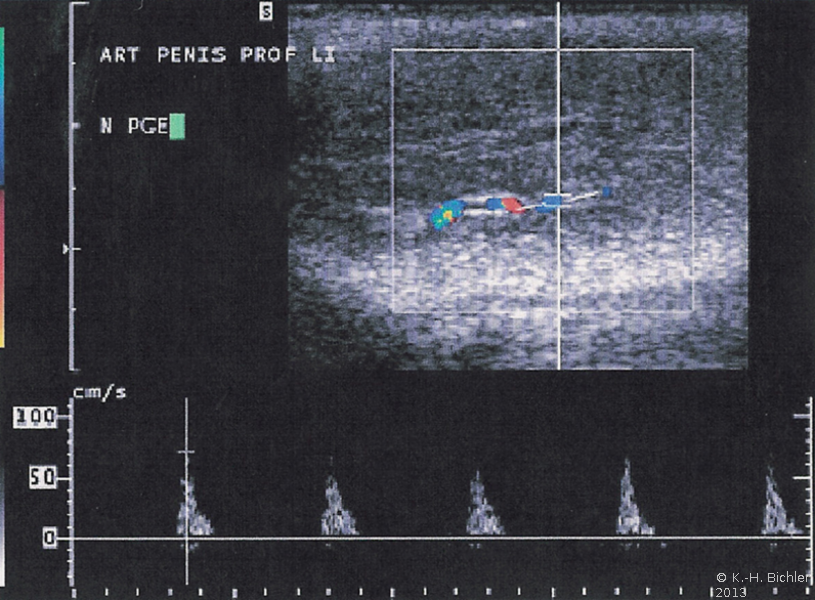

Über eine Farbdopplersonographie wird zunächst die Durchblutungssituation des Penis untersucht (Abbildung 3). Darüber hinaus werden im Notfall-Labor Blutuntersuchungen (Gerinnungsstatus, Differentialblutbild [Leukämie?], Blutzucker, kleines Blutbild) durchgeführt.